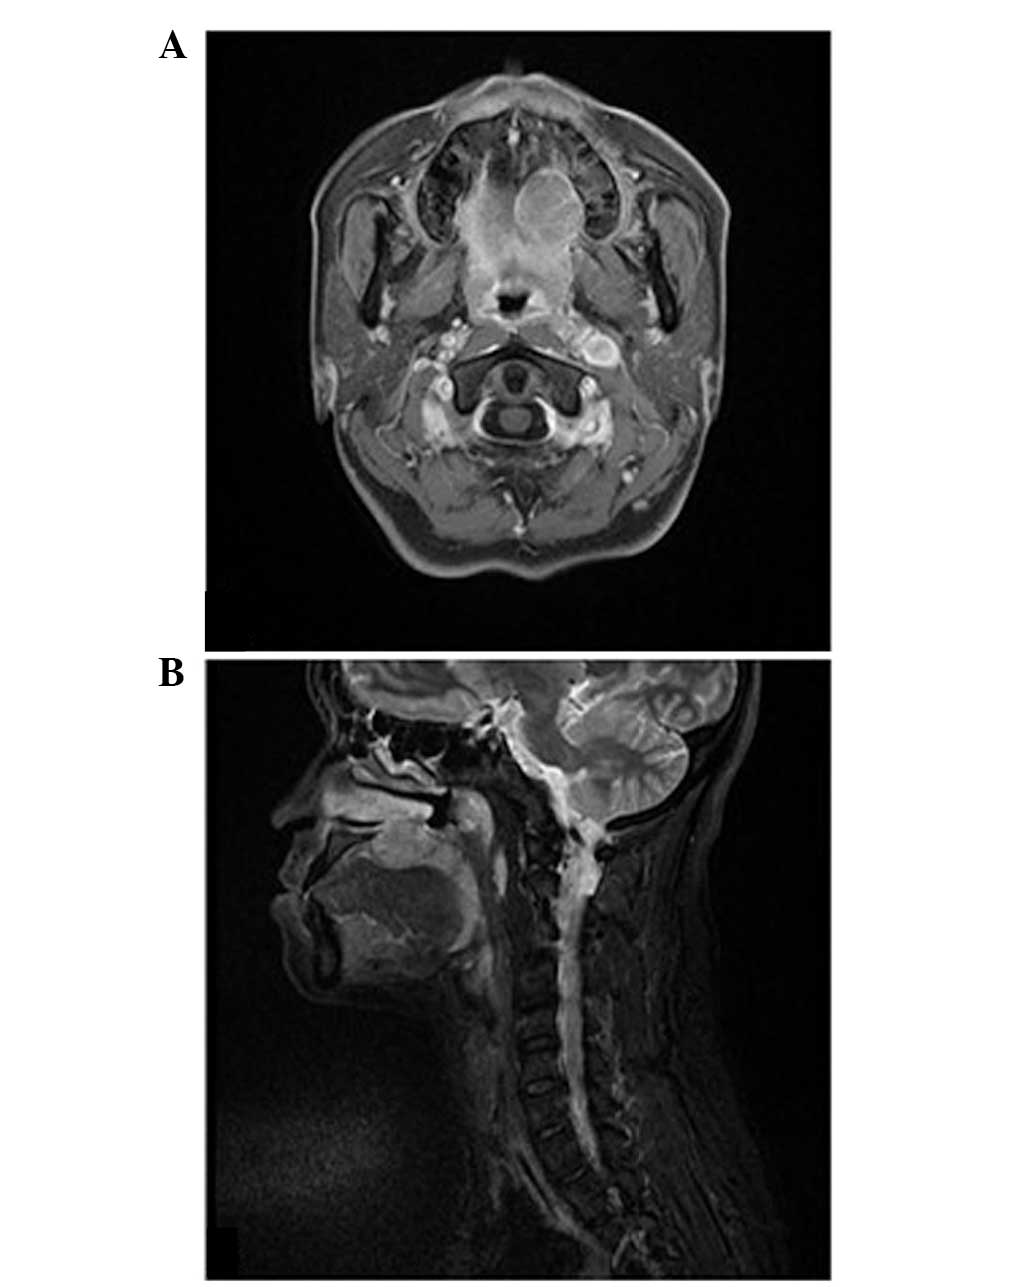

Figure 2

(A) Axial and (B) sagittal magnetic resonance images show a mass of 26 × 24 × 17 mm in size, located on the left hard palate with invasion into the nasal cavity.

A 38-year-old Chinese female was admitted to the Department of Stomatology at the Second Xiangya Hospital, of Central South University (Changsha, China) with a painless mass in her left palate. The patient stated that the mass was initially identified approximately one month previously. Intraoral examination revealed a well-defined, nodular mass in the left side of the hard palate (Fig. 1). The mass was non-tender and soft to palpation, with areas of fluctuance. The surface mucosa was red in color with no erosion, bleeding or ulceration. Magnetic resonance imaging delineated a mass lesion of 26 × 24 × 17 mm in size, located on the left hard palate with invasion into the nasal cavity (Fig. 2). The tumor exhibited isointensity on T1-weighted images and hyperintensity on T2-weighted images, with a moderately enhanced effect. No marked lymphadenopathy was identified according to imaging features and clinical examination. The patient was otherwise well, with no significant events in the medical history. An incisional biopsy was performed, which revealed irregular tumor nests of undifferentiated epithelial cells intimately intermingled with lymphocytes and plasma cells. The tumor cells exhibited a syncytial pattern with indistinct cell borders, vesicular nuclei, and large central nucleoli (Fig. 3). Immunohistochemically, the tumor cells were diffusely positive for cytokeratin AE1/AE3 (Fig. 4A). In situ hybridization for EBV-encoded RNA was diffusely positive in undifferentiated carcinoma, however, it was negative in the surrounding lymphoid stroma and adjacent salivary gland tissues (Fig. 4B). Endoscopy examination revealed a thickening of the nasopharynx. Multiple biopsies from the nasopharynx were subsequently performed, which were negative for tumor cells. A final diagnosis of primary LEC was determined. The patient underwent a partial maxillectomy without further surgical neck dissection. Adjuvant radiotherapy was suggested, however this was refused by the patient due to financial difficulties. The patient showed no evidence of remission during the postoperative follow-up of 12 months.